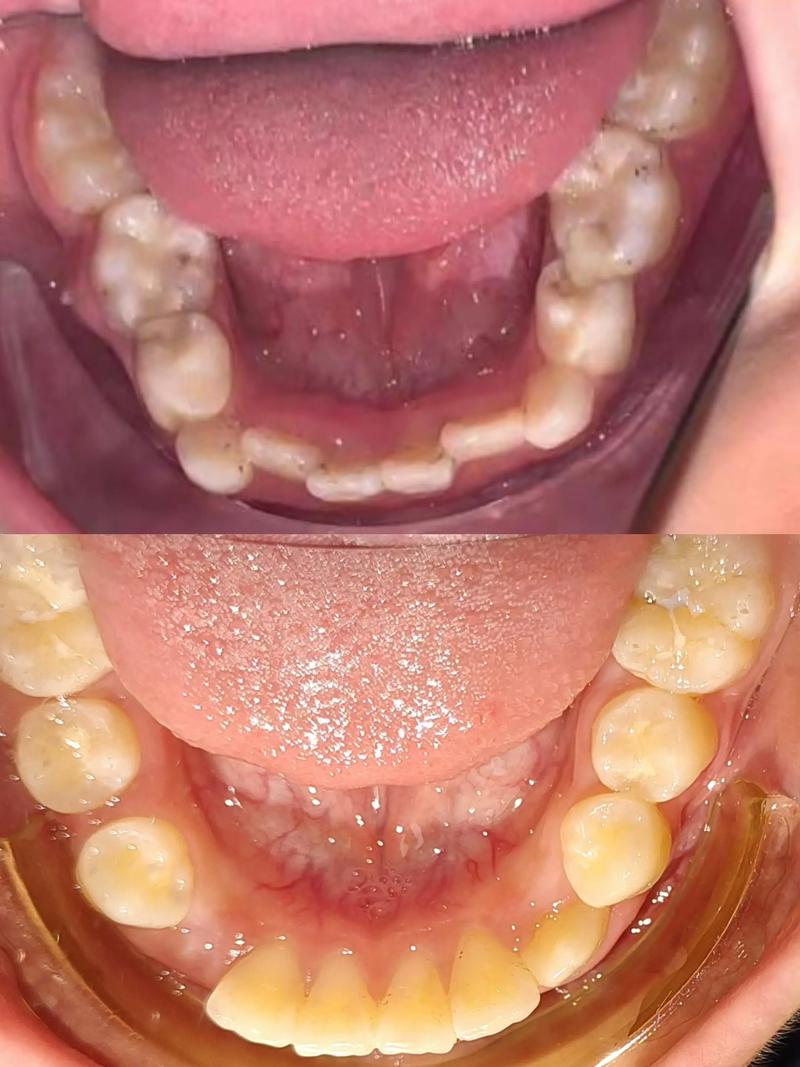

儿童牙齿矫正的核心在于“早期干预”与“综合治疗”,牙齿问题并非等换完牙再解决,而是根据不同年龄段的特点分阶段处理,比如乳牙期(3-5岁),若孩子存在“地包天”(反颌)、偏颌、下颌前突等问题,或长期吮指、咬唇、吐舌等不良习惯,可能影响颌骨发育和面部对称性,此时可通过简单矫正器(如活动矫治器、舌刺)纠正习惯,引导颌骨正常生长,替牙期(6-12岁)是“黄金干预期”,此时恒牙开始萌出,颌骨仍在发育,若出现“龅牙”(深覆盖)、牙齿拥挤、个别牙反颌、中线偏斜等问题,可利用生长潜力,通过功能矫治器(如FR矫治器、双垫矫治器)调整颌骨关系,为恒牙排列创造空间,恒牙早期(12岁后)则是“精细矫正期”,主要解决牙齿排列不齐、咬合紊乱等问题,以固定矫正或隐形矫正为主,通过精确移动牙齿达到功能与美观的统一。

针对不同类型的牙齿问题,矫正方法也各有侧重,以下是常见矫正方式的对比:

选择矫正方法时,需综合考虑孩子的牙齿问题、年龄、配合度及家庭经济条件,替牙期存在骨性问题的孩子,优先考虑功能矫治器,利用生长潜力调整颌骨;而恒牙期单纯牙齿排列不齐,则可根据预算选择金属托槽或隐形矫正。